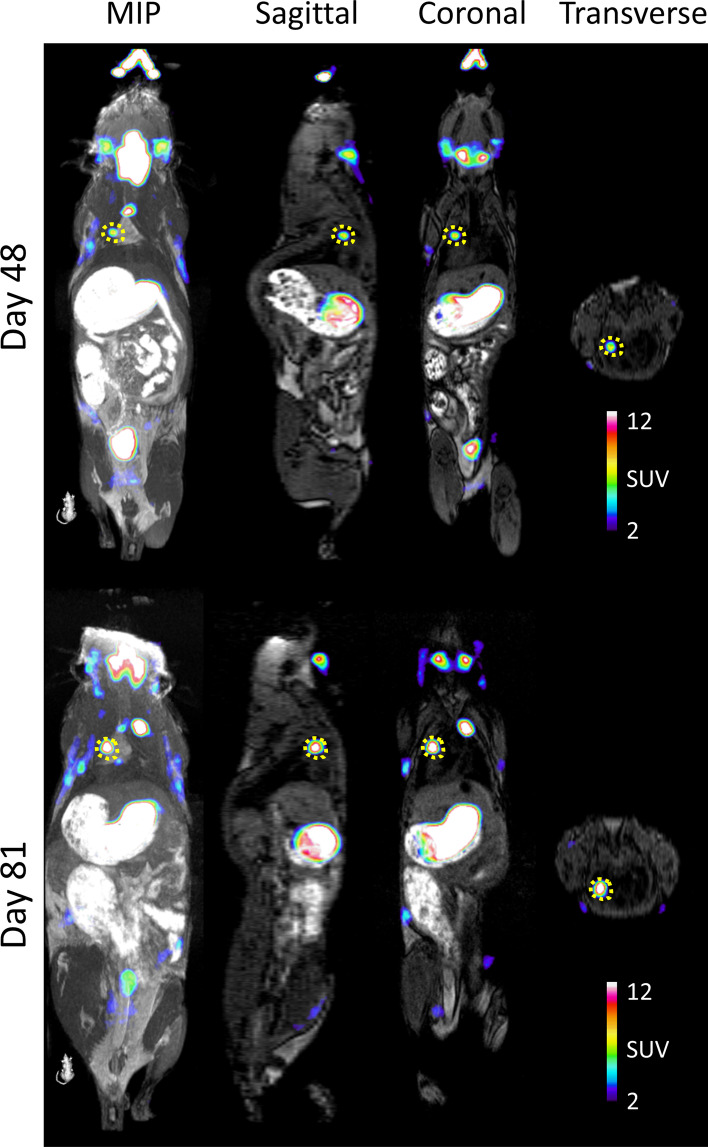

We were able to identify multiple small lung tumours with high [18F]TFB uptake as early as day 48 after tumour induction (Fig. 5); high tumour-to-normal lung contrast was observed. Further, we were able to follow lung tumour development longitudinally by performing repeated imaging (Fig. 8).

Fig. 8.

[18F]TFB PET imaging of NIS-expressing lung tumours over time. A small lung lesion is identified with a yellow dashed line. Orthogonal plane and a maximum intensity projection (MIP) are shown of the same mouse imaged at Day 48 and Day 81 after tumour cell transplantation